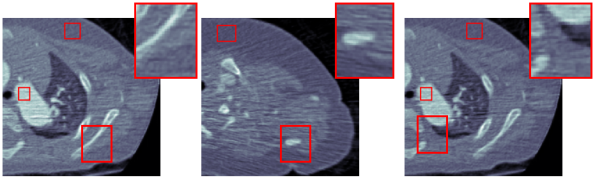

3.2 Qualitative Evaluation

We choose three representative low-dose CT images in the test dataset as shown in Fig. 3(a) for qualitative evaluation. The corresponding denoised images by CCADN, MCCAN without local cycles, MCCAN without global cycles, and MCCAN are shown in Fig. 3(b)- 3(e) respectively. Numbered areas are homogeneous regions, while areas with edges between heterogeneous regions are zoomed for visibility in Fig. 3. From the figures we can see that CCADN can successfully reduce noise in the original images. MCCAN without local cycles completely fails to produce reasonable results. A more closer examination of the images reveal that interestingly the background and the substances are approximately swapped compared with the original images. This is because the high-level features of content distribution are still kept even with such swap, and the discriminator cannot identify the generated image as “fake” because of the structure diversity in the training dataset. This aligns with our discussion on the importance of local cycles in Section 2. On the other hand, MCCAN without global cycles can successfully denoise the image and achieves similar quality compared with CCADN. This is expected as MCCAN without global cycles is essentially formed by two cascaded CCADNs. Finally, with both local and global cycles, the complete MCCAN has the smallest noise visually.

Five homogeneous areas chosen by radiologist are used for the quantitative evaluation, which are annotated by red rectangles in Fig. 3 and numbered from 1 to 5. The normalized quantitative results are shown in Table 1. CCADN can reduce the standard deviation in the five areas by 15%, 21%, 21%, 22% , and 22% respectively, with resulting mean values close to those of the original images. Although MCCAN without local cycles achieves smallest standard deviation in Areas 1, 3 and 4, it leads to meaningless output with large mean deviation from the original images, which corresponds to the structure loss in Fig. 3(c). MCCAN without global cycles has similar performance compared with CCADN. with mean values close to original and standard deviation reduction by 22%, 23%, 20%, 27%, and 19% respectively. Finally, the complete MCCAN behaves the best among all the methods: Within reasonable mean range, the standard deviations are decreased the most by 24%, 32%, 29%, 29%, and 32% from the original CT images respectively.